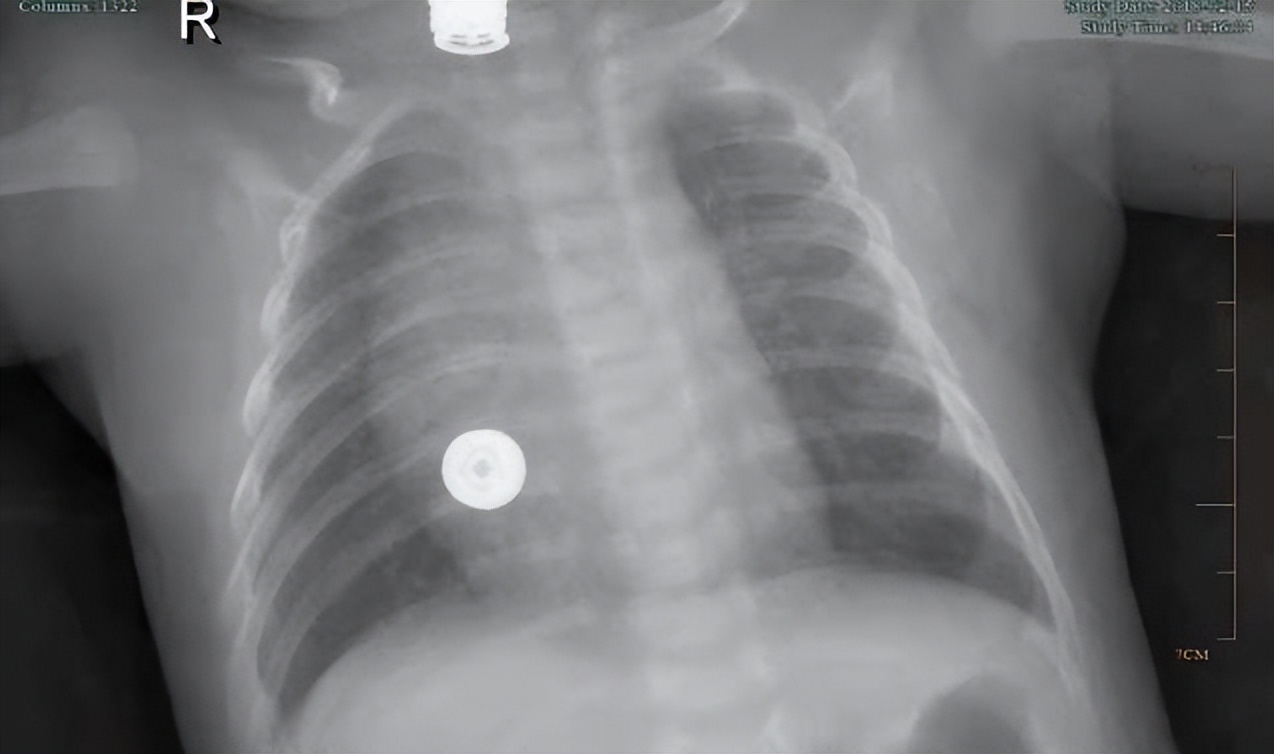

其中胸片结果提示患儿肺部有弥漫性的模糊影,符合支气管肺炎改变。实验室检查提示:白细胞12.3*10^9/L,增多;血红蛋白109g/L,降低;超敏CRP全血快速定量2.72mg/L,增多;呼吸道病毒三联快检示呼吸道合胞病毒阳性,提示RSV感染。

经过一周住院治疗,患儿体温逐渐恢复正常,胸片恢复正常,遂顺利出院。

查体提示孩子呼吸平稳,口周无发绀,咽无充血,扁桃体无肿大。双肺呼吸音粗,未闻及明显干湿性啰音,复查血常规白细胞恢复正常水平,胸片恢复正常。